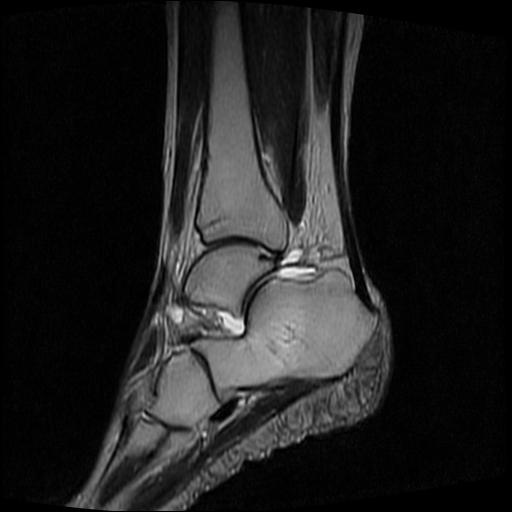

标题: MRI0968:女性,70岁,跟骨信号异常 [打印本页]

标题: MRI0968:女性,70岁,跟骨信号异常

女性,70岁,右侧跟骨疼痛2个月,负重时加剧,不负重时不疼。

胫骨下段,跟骨、距骨可见斑片状异常信号区;考虑:转移瘤

跟骨病灶呈片状,边界模糊,可否考虑隐匿性骨折呢?

跟骨长t1长t2信号异常,边缘模糊(肿瘤一般边界清楚,故肿瘤不考虑),压脂像呈高信号--骨髓水肿(炎症?)。